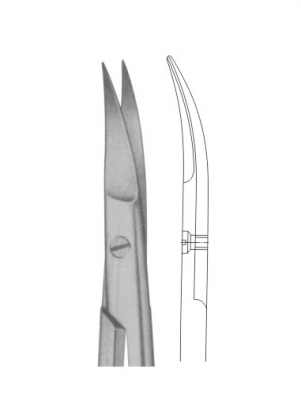

- Scissors